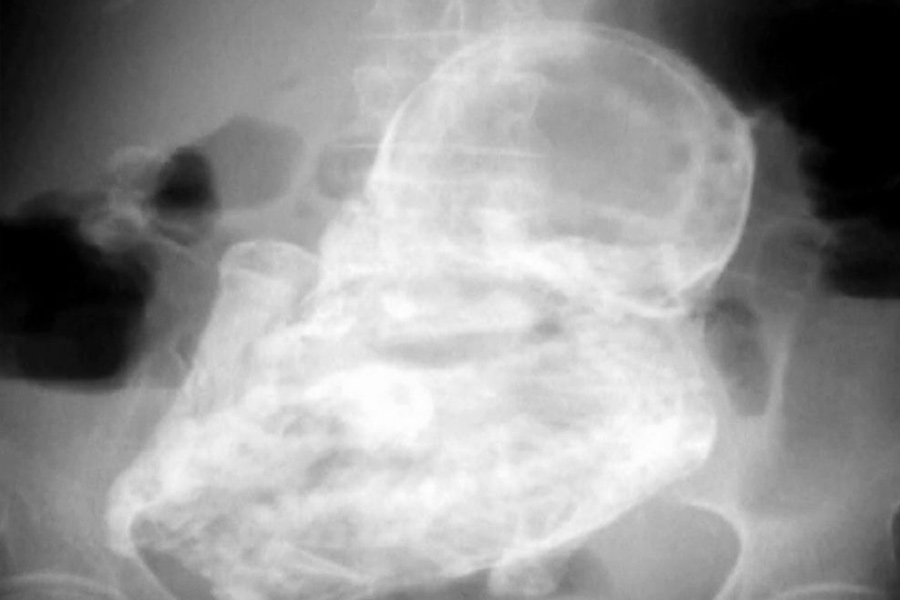

Representational picture of X-ray

কলম্বিয়ার ওই বৃদ্ধার পেটে পাথুরে ভ্রূণের সম্পর্কে সংবাদমাধ্যমে শোরগোল পড়েছিল ২০১৩ সালের ডিসেম্বরে। সংবাদমাধ্যমের দাবি, প্রায় ৪ দশক ধরে এর অস্তিত্ব সম্পর্কে কোনও ধারণাই ছিল না বৃদ্ধার।

চিকিৎসকেরা জানিয়েছিলেন, ওই বৃদ্ধার তলপেটের এক্স-রে করানো হলে তাতে ধরা পড়ে ‘লিথোপেডিওন’ হয়েছে তাঁর। চিকিৎসকদের পরিভাষায় যা অতি বিরল ঘটনা। একে ‘স্টোন বেবি’ও বলেন তাঁরা।

Picture of x-ray

একটি রিপোর্টের দাবি, গর্ভের বাইরে ভ্রূণের জন্মের পর তা ‘লিথোপেডিওন’-এ পরিণত হওয়ার ঘটনা ১.৫ থেকে ১.৮ শতাংশের মধ্যে ধরা পড়েছে।